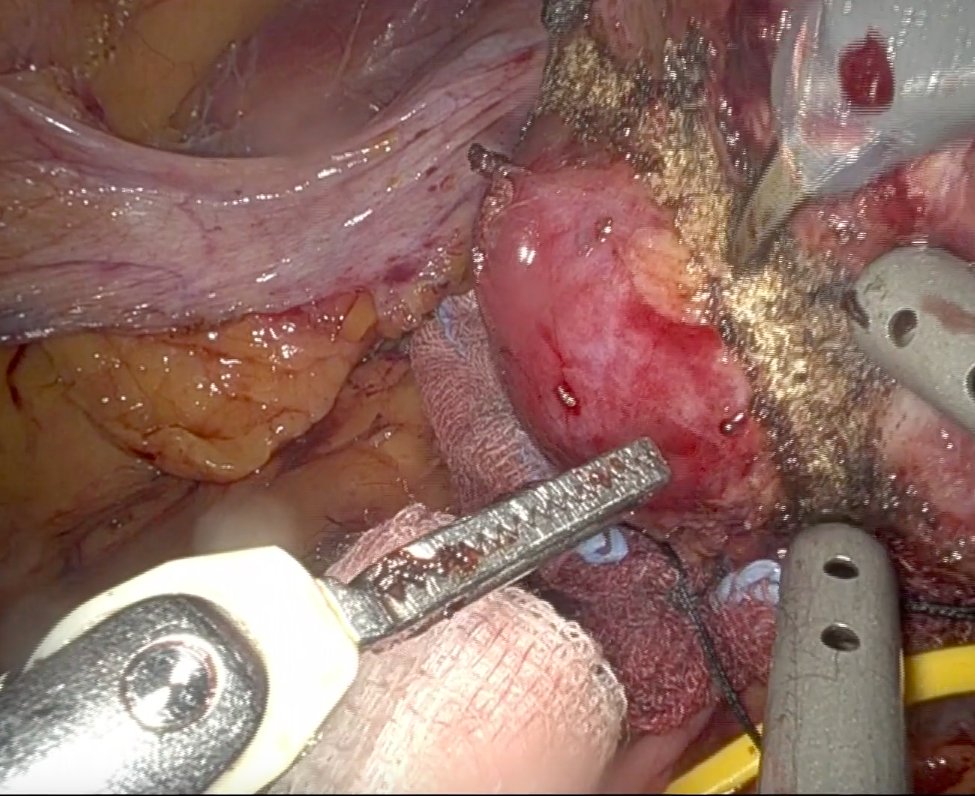

New Edition Verona 13-14 June 2025 Cadaverlab Hands On in Laparoscopic Urological Surgery for the School of Residency in Urology, Sapienza University of Rome. Surgical procedures for radical nephrectomy and radical prostatectomy trainees. Sapienza Policlinico Umberto I European Association of Urology (EAU)

5th Cadaverlab hands on Laparoscopic surgery SAPIENZA UNIVERSITÀ Urologic Residency School ROME. Procedures performed by Residents III IV year: radical nefrectomy - radical prostatectomy. Focus on surgical anatomy and Laparoscopic steps in Major surgery. Sapienza Università di Roma